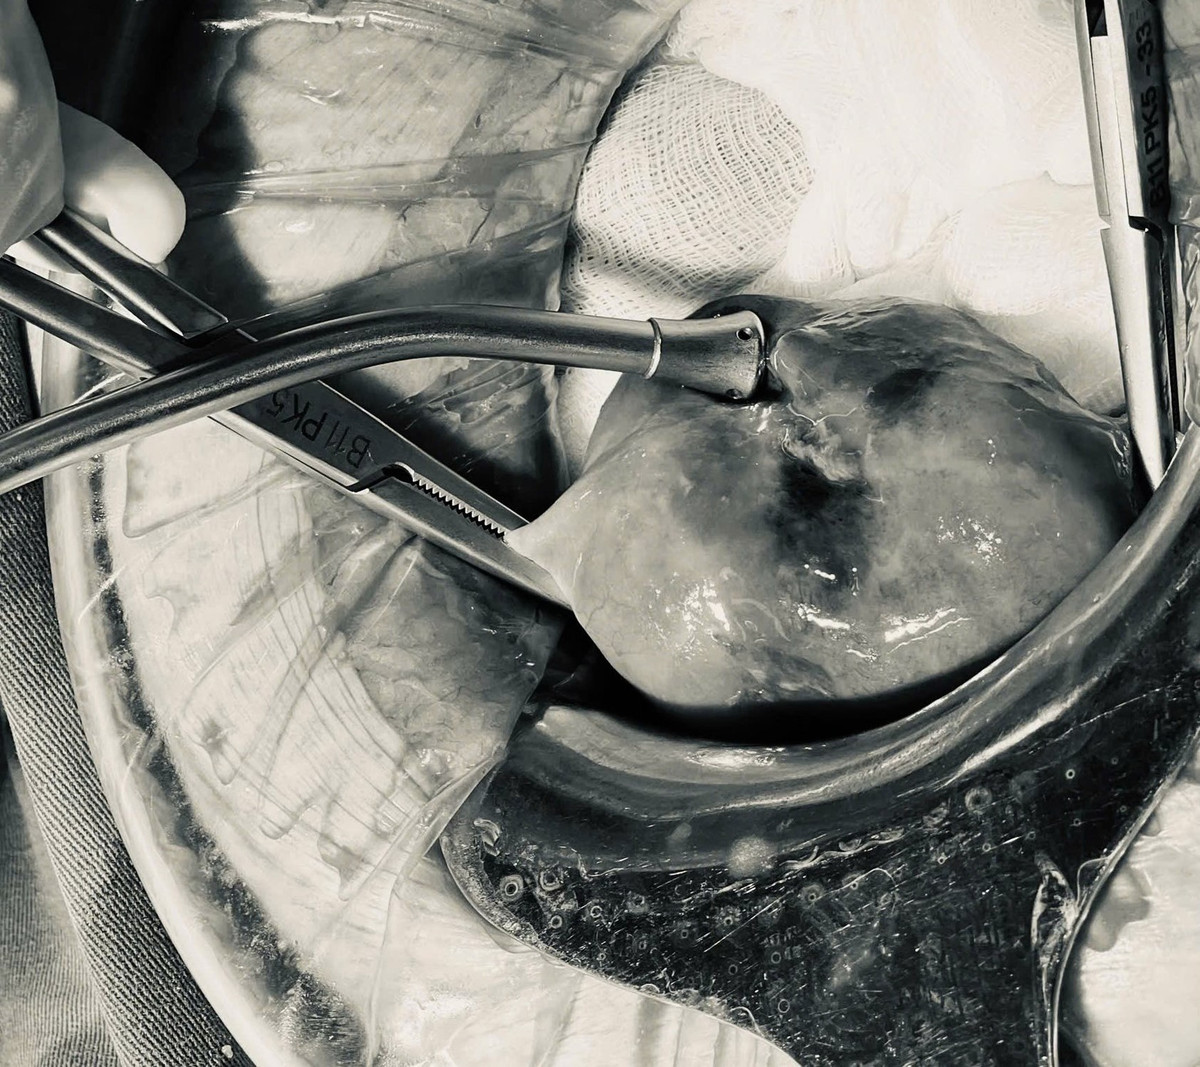

thung-tu-cung-1-3113.jpg

Tử cung đã được cắt bỏ - Ảnh BVCC

Nhận thấy tình trạng nặng trên một bệnh nhân lớn tuổi, thể trạng kém, nhiều bệnh lý nền, nguy cơ sốc nhiễm khuẩn, các bác sĩ của Khoa Phụ sản - Bệnh viện Trung ương Quân đội 108 đã nhanh chóng tiến hành phẫu thuật cấp cứu mở bụng, thấy toàn bộ ổ bụng là dịch mủ hôi, chảy ra từ lỗ thủng vùng đáy tử cung, các quai ruột dính thành đám.

Ê-kíp phẫu thuật đã cắt bỏ hoàn toàn tử cung và 2 phần phụ, lau rửa ổ bụng giải quyết ổ nhiễm khuẩn. Bệnh nhân được điều trị kháng sinh và chăm sóc tích cực, nâng đỡ thể trạng, bệnh nhân đã ổn định và xuất viện sau 10 ngày.